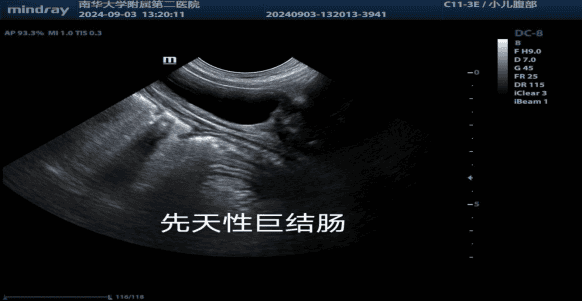

7、小儿亚专业组

主要疾病诊断包括:小儿髋关节发育不良、新生儿颅脑超声、新生儿肺部超声、肠系膜淋巴结、婴幼儿先心病、肠梗阻、肠套叠、肠旋转不良、幽门肥厚性狭窄、脑出血、斜颈等。